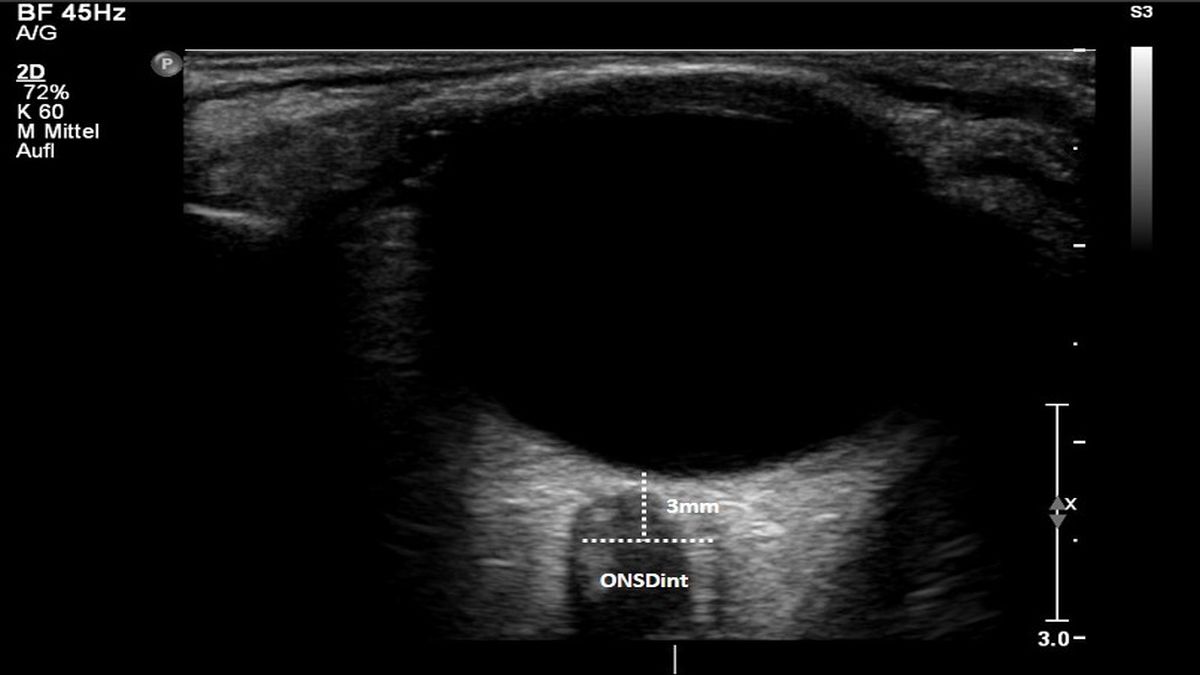

Ultraschall durchs Augenlid erkennt gefährlichen Hirndruck